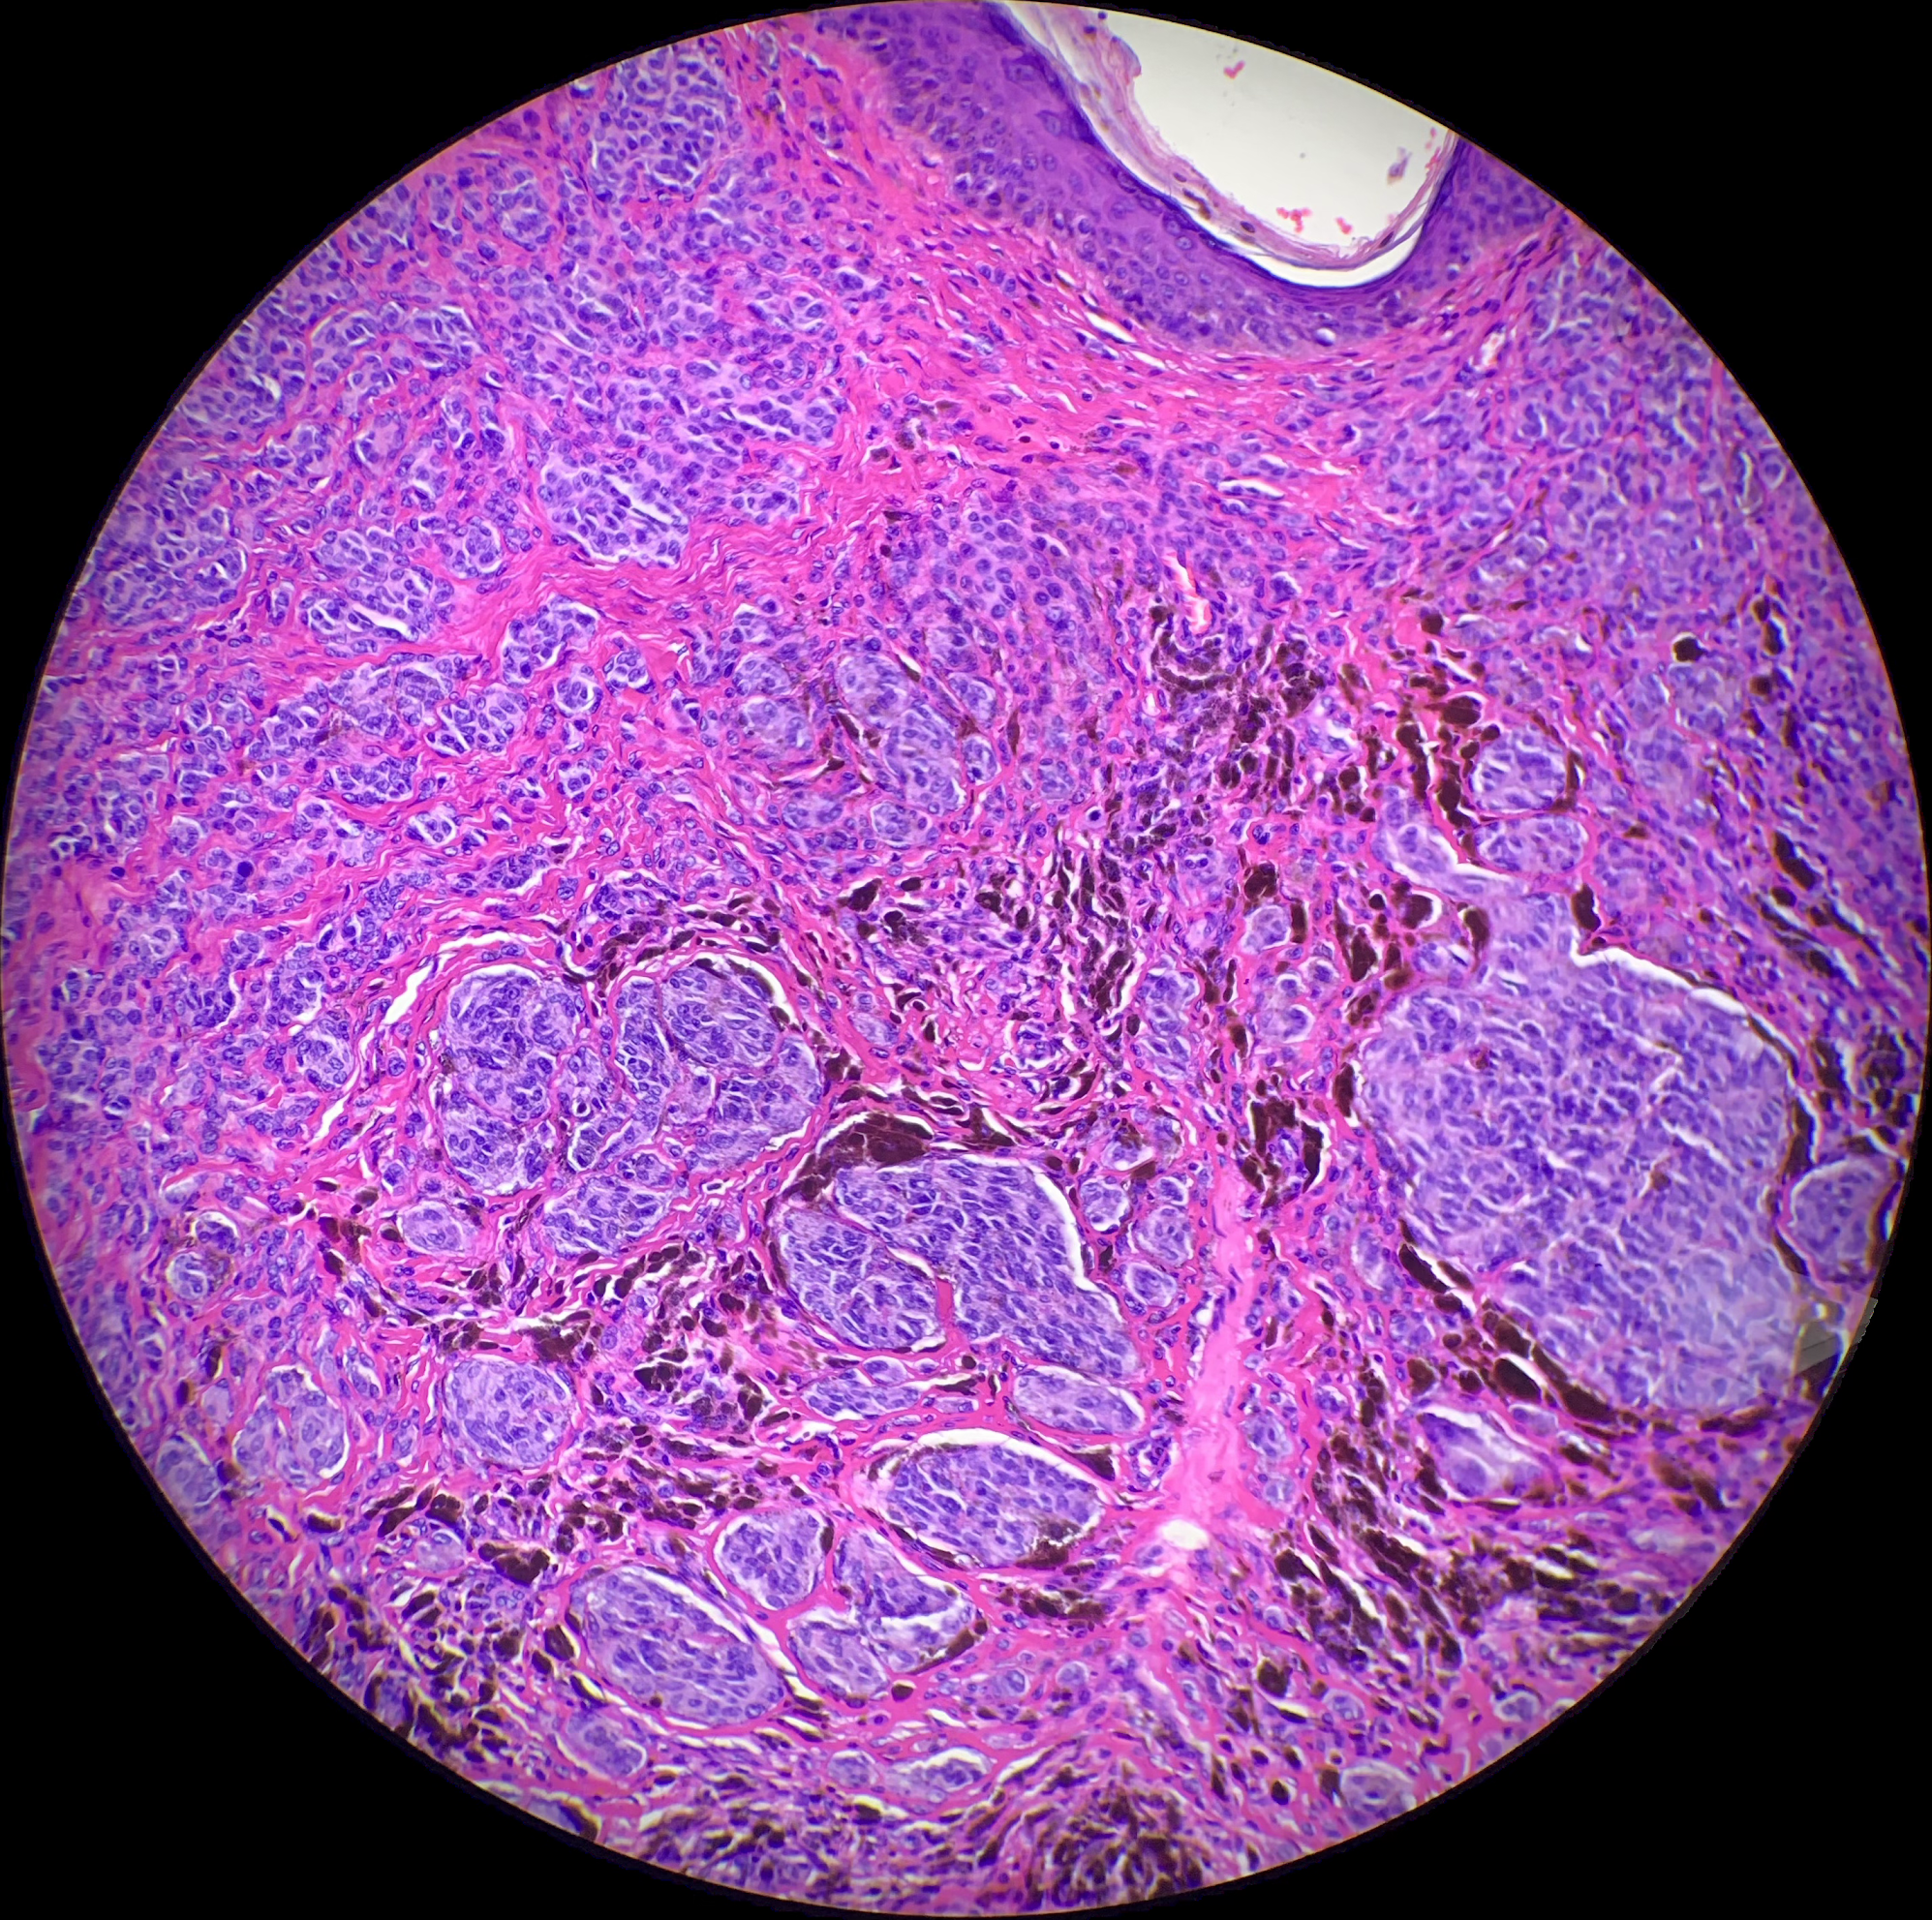

MD, Dermatopathologist

Microscopy